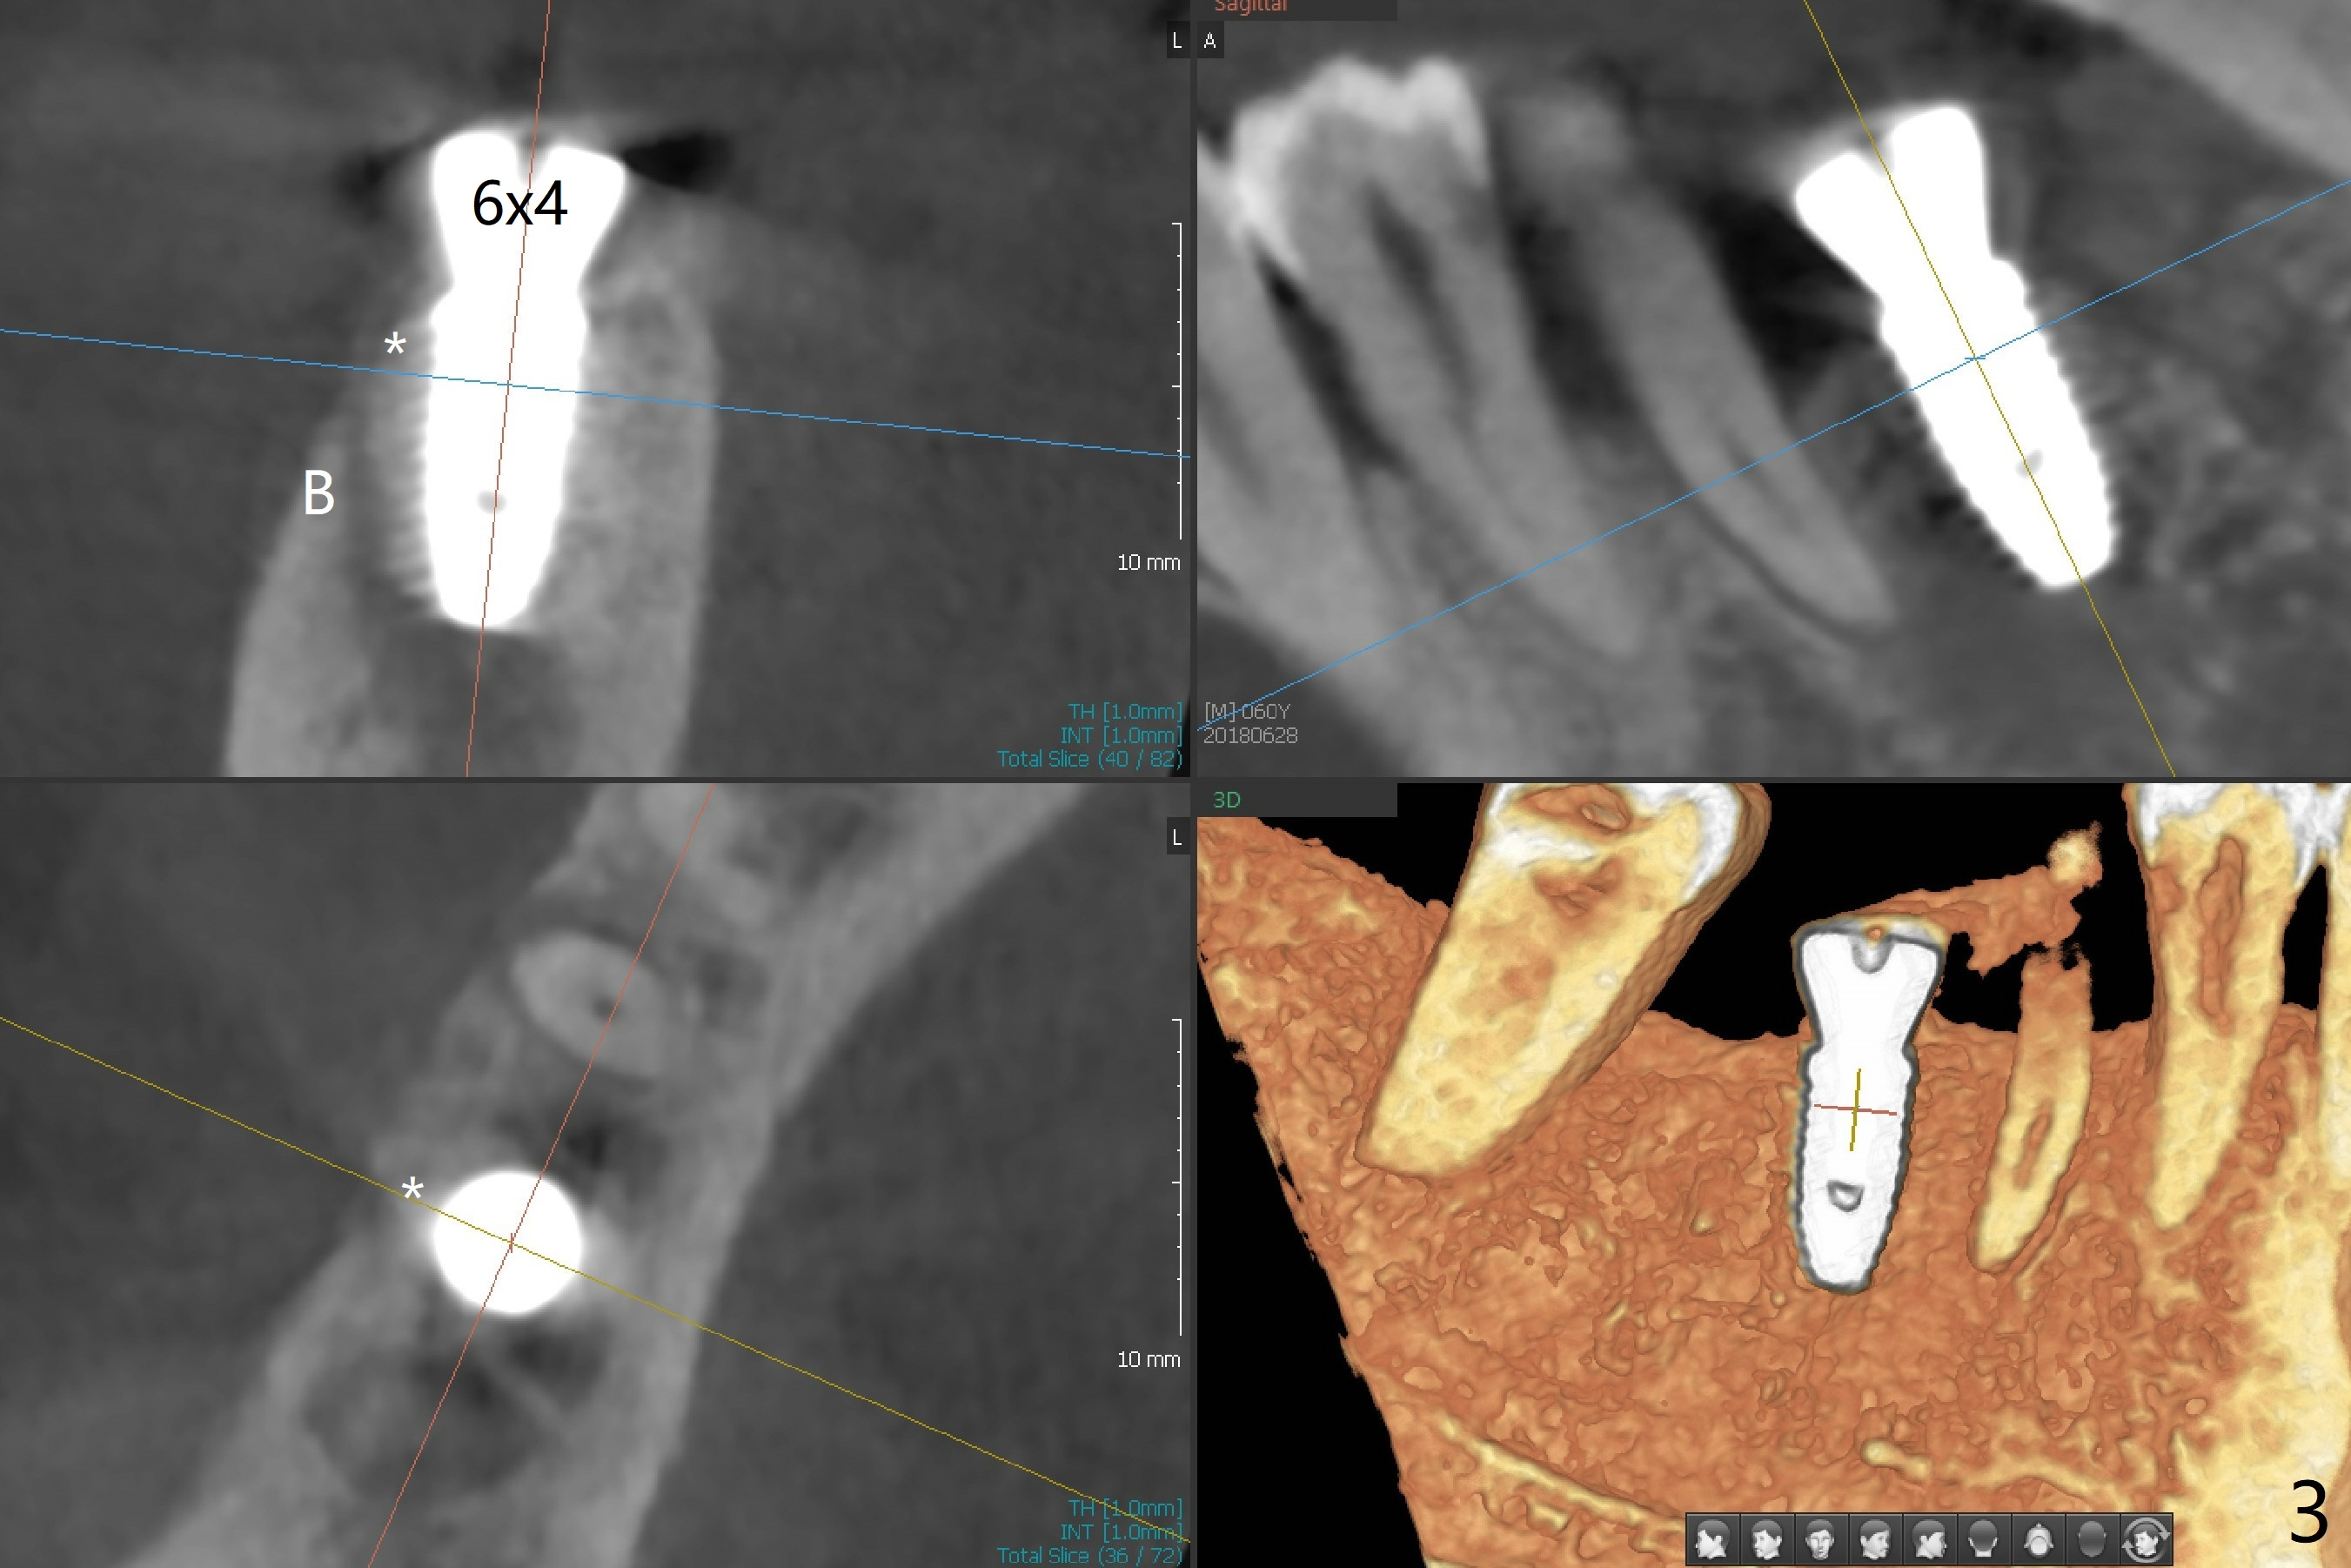

There are two questions before guided surgery at #30.  First, is implant placement 3 months post socket preservation too early?  Will the periapical radiolucency between #29 and #30 affect osteointegration?  Reanalysis of CT >2 months post socket preservation reveals that the lamina dura of the tooth #29 is apparently intact (Fig.1).  Immediately preop clinical exam shows no active infection.  The patient is reluctant to accept RCT at #29.  A 5x10 mm implant is placed slightly subcrestal buccally (which is the lowest, Fig.2).  Immediately postop CT (5x5cm field of view) demonstrates that the implant is covered by graft bone (Fig.3 *) buccally (B).  In fact the autogenous bone harvested from osteotomy is inserted between the 6x4 mm healing abutment and the buccal gingiva.